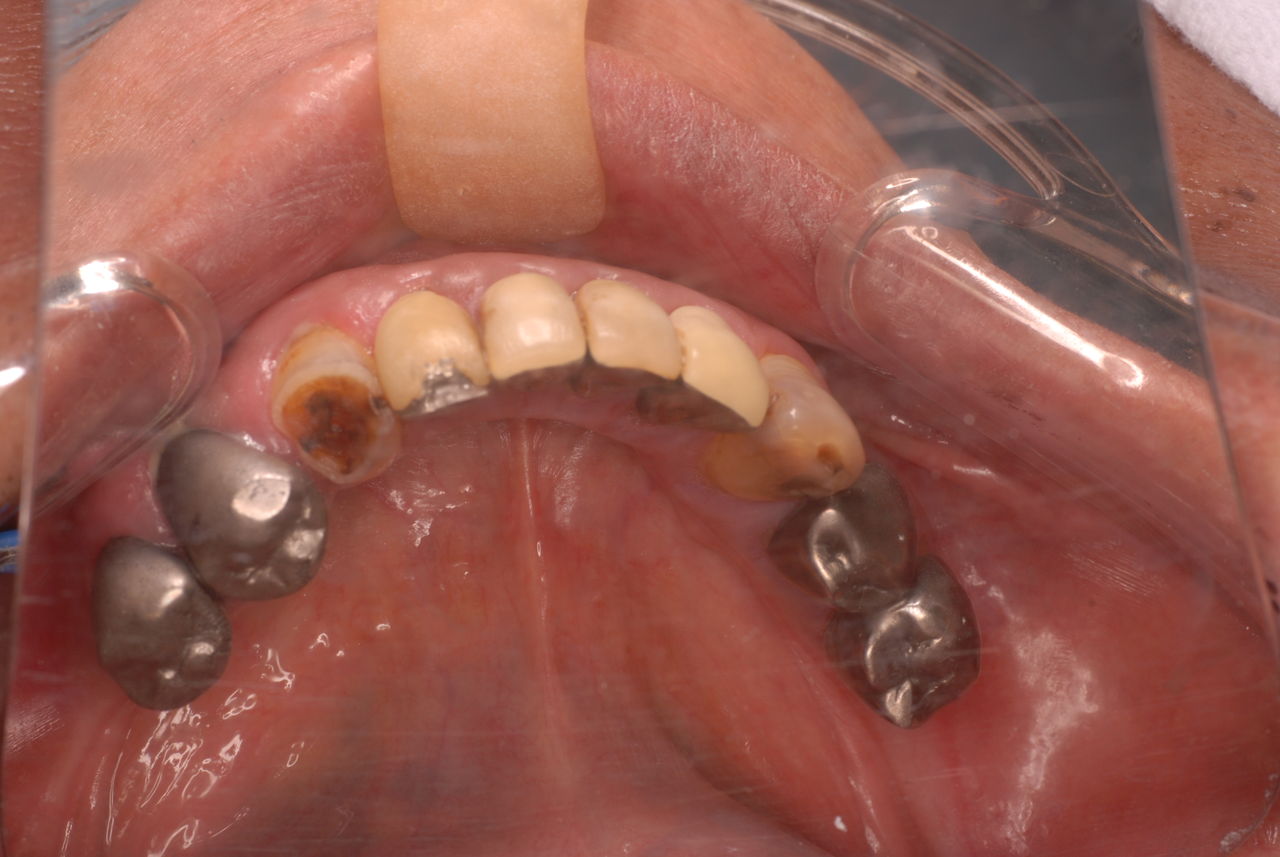

カビか何かが入り込んでいる異様な入れ歯でした。

上の歯は一本がブラブラでしたね。

カビのような汚い部分を除去した直後です。

下顎です。